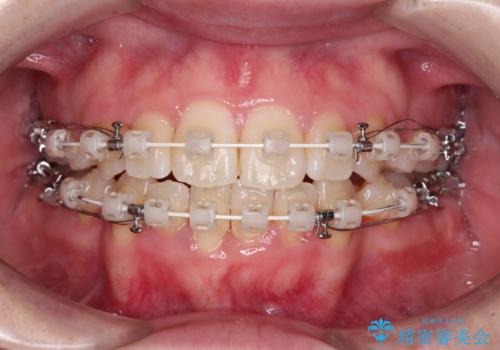

- 矯正装置

- 審美装置

- 2年2ヶ月

舌の突出癖を改善するためのトレーニングをしっかりと行っていただいたことで、比較的スムーズに治療を進めることができました。

口元の突出感もしっかりと改善することができました。